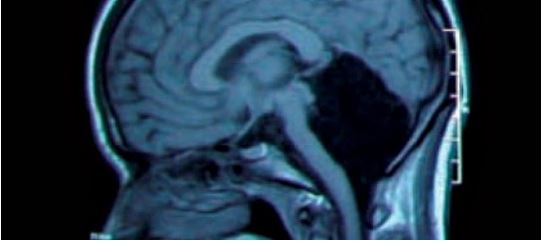

Ajo që ata padyshim nuk prisnin ishte që në vendin ku duhet të gjendjej celebrum, truri i madh, s’kishte asgjë. Kjo pjesë e trurit, që kontrollon ekuilibrin, lëvizjen dhe aftësitë për të mësuar dhe një pjesë të të folurit, përbën rreth 10 përqind të masës totale të trurit të njeriut.

Ekspertët dyshojnë se çfarëdolloj gjëje që ka shkaktuar zhdukjen e celebrum –it ka ndodhur në moshë të vogël, duke i dhënë kështu mundësinë trurit që të adaptohet me gjendjen.

Me pak fjalë, pjesa tjetër e trurit mori nën kontroll pjesën që mungonte, duke mbushur boshllëkun.